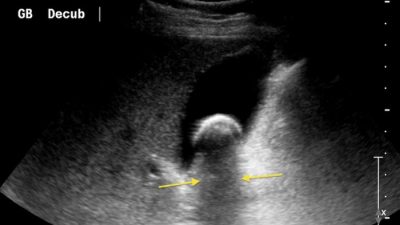

cara membaca hasil USG

Cara Membaca Hasil USG Batu Empedu: Panduan Langkah demi Langkah